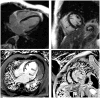

Cardiac involvement in patients with muscular dystrophies: magnetic resonance imaging phenotype and genotypic considerations